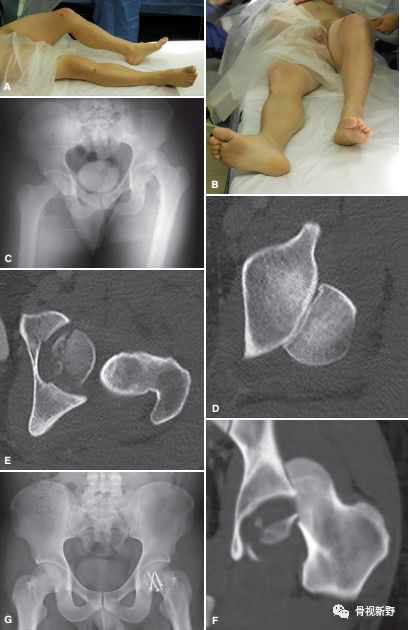

髋关节后脱位往往合并股骨头骨折(5-15%)。最早(1957年)由Pipkin描述并分类,因而被命名为Pipkin骨折。

pipkin分型

对I、II型,应尽早(6-12h)试行手法复位(复位方法同单纯髋关节后脱位复位方法,如下图)。

Cases

Pipkin-I 型(S-P入路)

Pipkin-IV型(Ganz入路)